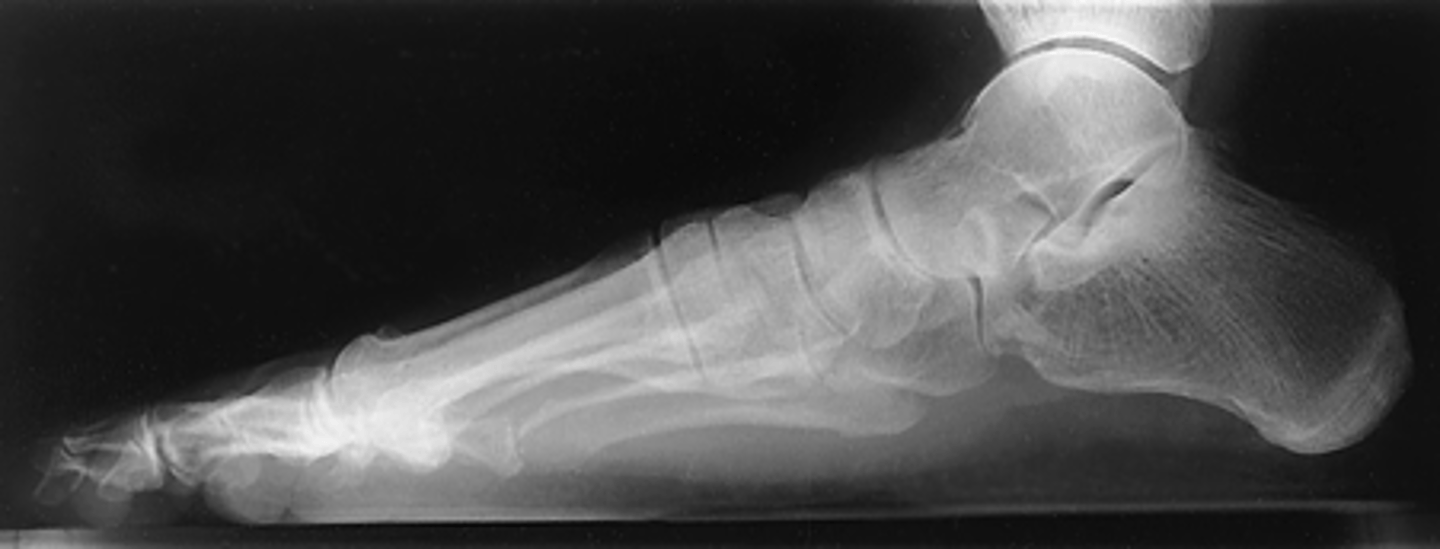

Mediolateral Foot

What projection is this?

Evaluation Criteria for Mediolateral Foot

- True lateral

- CR to midcuneiform (base of third MT)

- Entire foot visualized

- Tibiotalar joint demonstrated

- Metatarsals superimposed

- Optimal exposure factors